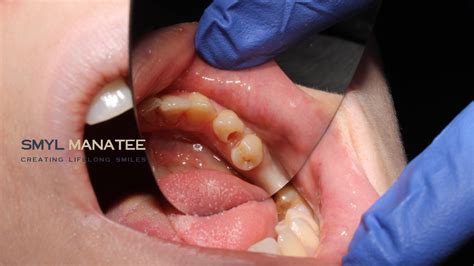

- Small holes or pits (cavities) on the surface of the enamel.

| Stage 2: Dentin Decay | Brown/Black spots | Composite resin fillings |

| Stage 3: Advanced Decay | Visible cavity/Pain | Dental crowns or veneers |